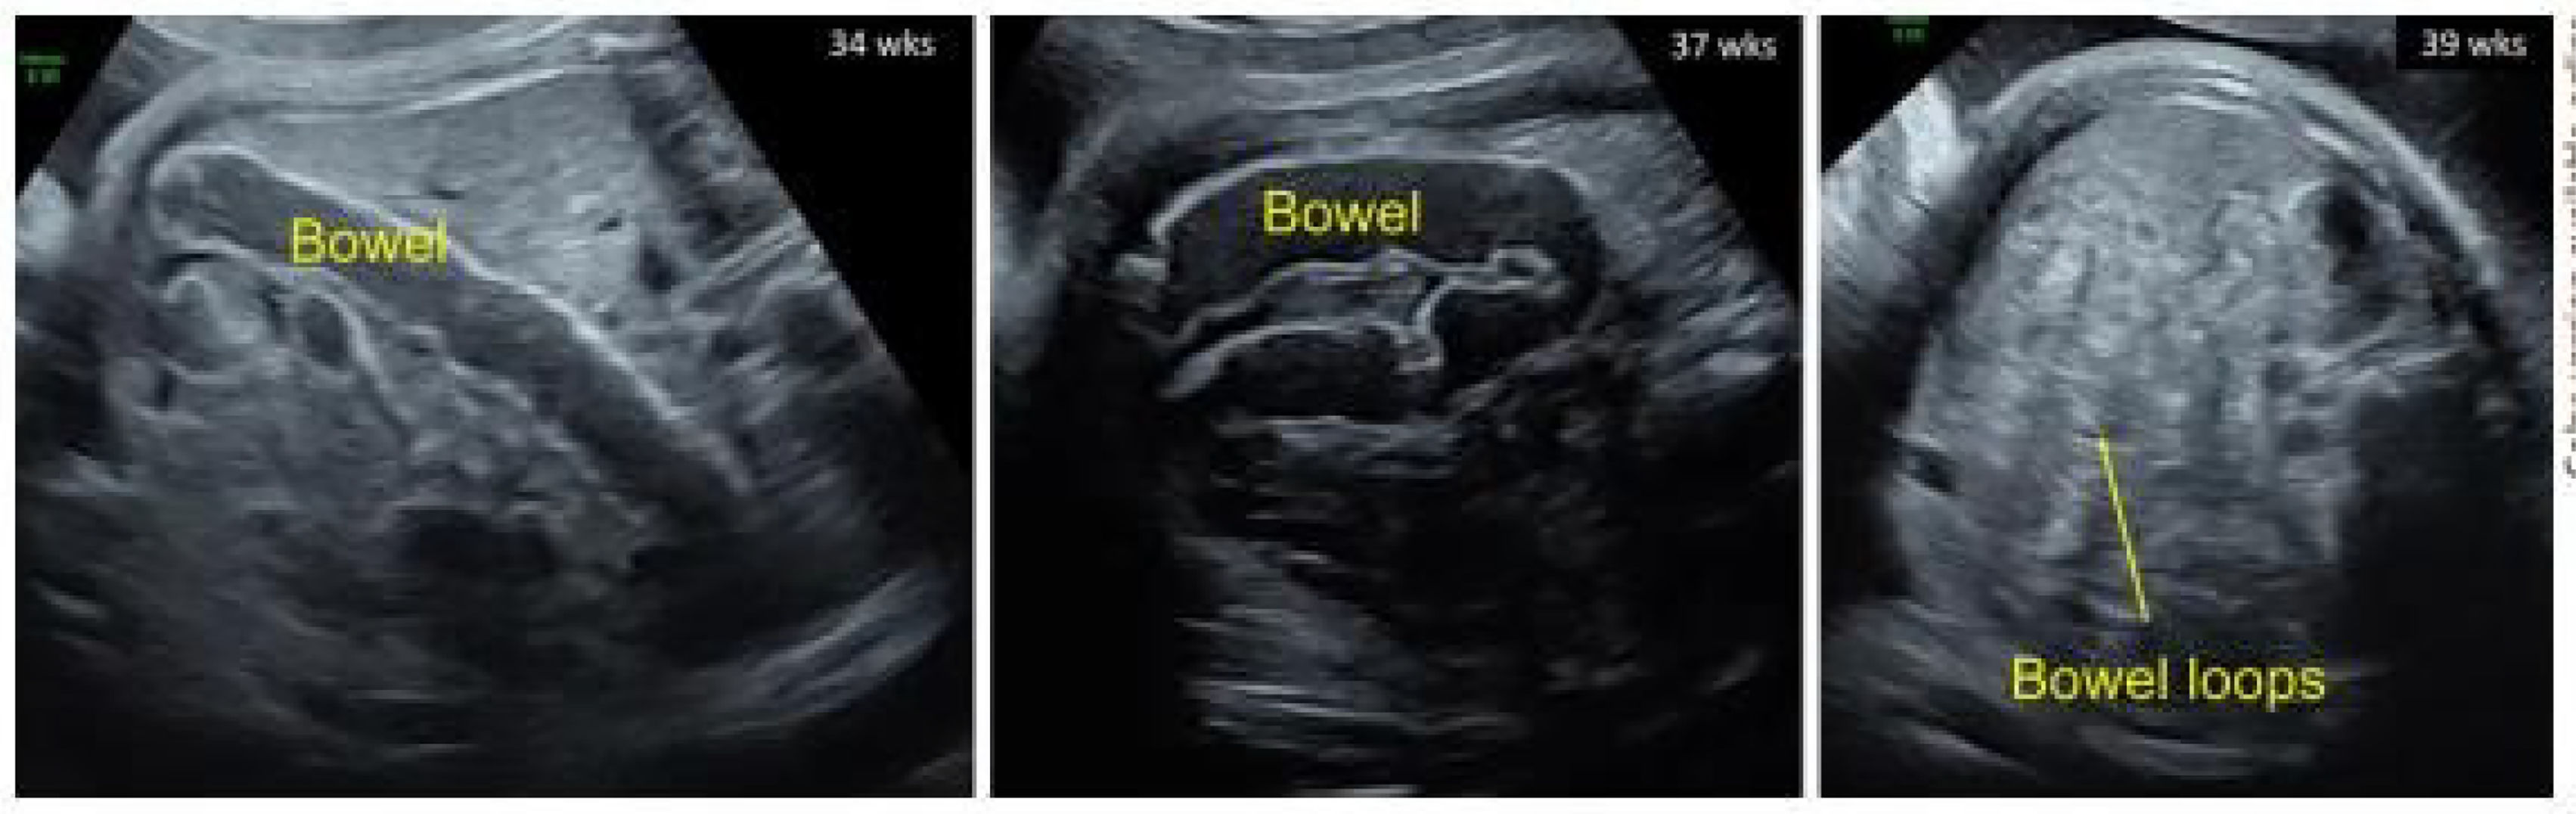

Case descriptionA 32-year-old woman attended a pregnancy check-up during which an ultrasound revealed a hyperechoic intestine in the foetus at 21 weeks (2nd trimester). During the follow-up examination, dilation of the foetal large intestine was observed in the transverse and descending colon, accompanied by poor peristaltic movement. This obstruction and dilation of the intestinal walls can result in intrauterine complications, such as intestinal perforation leading to meconium peritonitis, or polyhydramnios. A genetic study showed that both parents were carriers of the F508del CFTR mutation. At 26 + 2 weeks of gestation, amniocentesis confirmed that the foetus was affected by CF and carried the homozygous F508del CFTR mutation.

Treatment was started at 31 + 1 weeks. The regimen used was for patients of at least 30 kg: 2 tablets of IVA/TEZ/ELX 75/50/100 mg in the morning and 1 tablet of ivacaftor 150 mg at night. During pregnancy, the mother's liver function remained normal, and the only potential adverse effect was a skin rash. A biopsy identified the rash as acute folliculitis. The foetal intestine remained unchanged until week 39, when it was observed that the dilation had resolved (Figs. 1 and 2).4